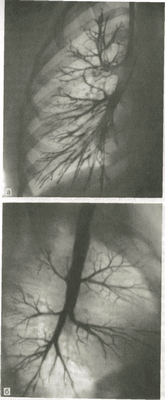

В связи с развитием КТ и бронхоскопии значительно сузились показания к специальному рентгенологическому исследованию бронхов — бронхографии. Бронхография заключается в искусственном контрастировании бронхиального дерева рентгеноконтрастными веществами (рис.6). В клинической практике показанием к ее выполнению является подозрение на наличие аномалии развития бронхов, а также внутреннего бронхиального или бронхоплеврального свища. В качестве контрастного вещества применяют пропилйодон в виде масляной взвеси или водорастворимый йодистый препарат. Исследование проводят преимущественно под местной анестезией дыхательных путей с помощью 1 % раствора дикаина или лидо-каина, но в отдельных случаях, главным образом при выполнении бронхографии у маленьких детей, прибегают к внутривенному или ингаляционному наркозу. Контрастное вещество вводят через рентгеноконтрастные катетеры, которые хорошо видны при рентгеноскопии. Некоторые типы катетеров имеют систему управления концевой частью, что позволяет вводить катетер в любые участки бронхиального дерева.

При анализе бронхограмм идентифицируют каждый контрастированный бронх, определяют положение, форму, калибр и очертания всех бронхов (рис. 6). Нормальный бронх имеет конусовидную форму, отходит от более крупного ствола под острым углом и под такими же углами отдает ряд последующих ветвей. В начальной части бронховII и III порядков нередко отмечаются неглубокие циркулярные перетяжки, соответствующие местам расположения физиологических сфинктеров. Контуры тени бронха ровные или слегка волнистые.

Рис.6. Бронхограммы правого легкого и схемы к ним.

а - прямая проекция; б - боковая проекция; 1 - верхушечный бронх 2 - задний - передний, 4 - наружный, 5 - внутренний, 6 - верхний нижней доли 7 - ниж-невнутреннии, 8 - нижнепередний, 9 - нижнёнаружный, 10 - нижнезадний.